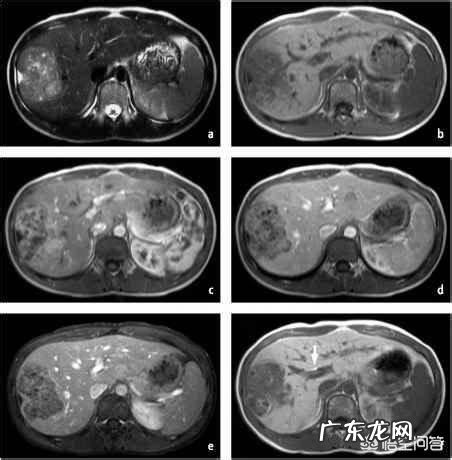

有条件的情况下也可以使用MRI增强扫描,无电离辐射,能够发现足够小的肝癌,甚至对于癌前病变,比如肝硬化结节,退变结节等进行追踪和评估,而且可做到一站式检查,定位,定性,术前评估等 。